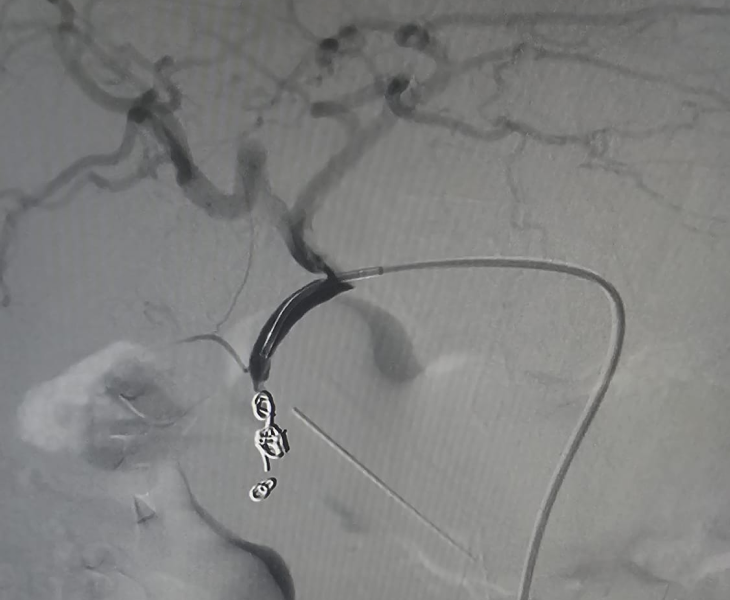

- Catheter angiography: contrast is injected to locate the pseudoaneurysm and bleeding source.

- Super‑selective catheterisation: a microcatheter is advanced into the specific branch feeding the pseudoaneurysm.

- Embolization: coils and/or other embolic agents are deployed to stop blood flow to the pseudoaneurysm.

- Post‑embolization check: repeat angiography confirms complete sealing with preserved flow to normal tissues.